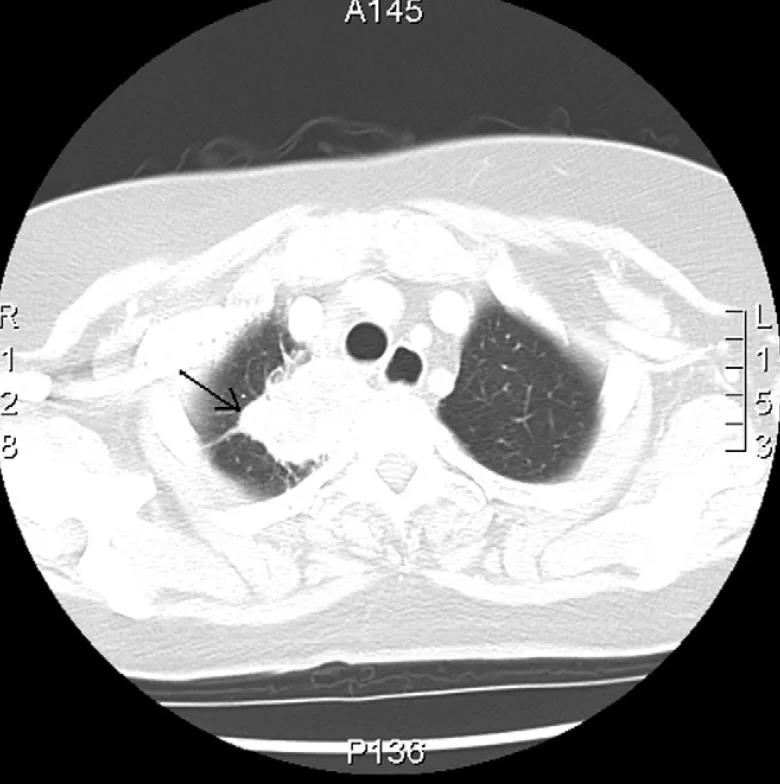

在国外文献中,如上所述最终发现引起丑角综合征的始作俑者为肺尖肿瘤(Pancoast 瘤、肺上沟癌)的报道更是屈指可数。其中一例因反复发作性胸痛、右肩痛的 74 岁女性一开始被误诊为急性冠脉综合征,一波三折之后,最终正是因为「丑角综合征现身」而及时通过胸部 CT 发现是右肺尖肿瘤在作祟 [7]。